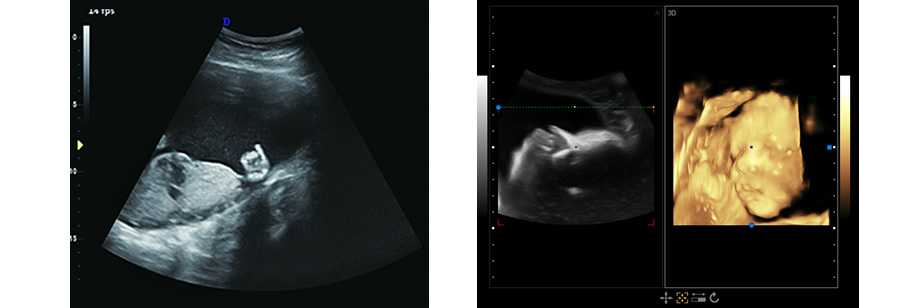

DW-T6全身應用型彩色多普勒超聲診斷系統,采用全新的技術平臺,基于安全、穩定的操作系統從容應對各種突發狀況; 高性能、低功耗工控解決方案,保證更佳圖像性能的清晰呈現。高亮度、高分辨率彩色醫用液晶顯示器;高靈敏度超大觸摸屏,讓醫生在臨床應用中享受更多的操作樂趣。

1.廣泛應用于腹部、泌尿科、婦產科、兒科/新生兒科、淺表組織、肌肉骨骼心臟等